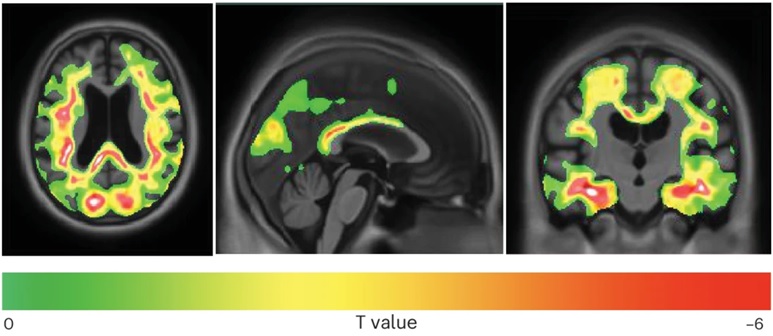

Mối tương quan ngược chiều giữa tỷ lệ STA và t-tau với sự tích tụ tau-PET ở vùng não (ảnh: Nature Medicine).

Trước đó, GS Thomas Karikari cũng đã phát hiện một dạng tau đặc hiệu của não gọi là BD-tau, có thể đo được trong máu và chỉ ra sự hiện diện của thoái hóa thần kinh. Ngoài ra, các dạng tau phosphoryl hóa đặc hiệu như p-tau181, p-tau217 và p-tau212 trong máu cũng có thể dự đoán sự hiện diện của amyloid-beta trong não mà không cần phải thực hiện các xét nghiệm hình ảnh não tốn kém. Tuy nhiên, việc phát hiện sớm tau vẫn là một thách thức lớn. Xét nghiệm tau-PET hiện nay là công cụ chính xác để đo mức độ tau trong não, nhưng hạn chế về chi phí, độ phân giải và nhân lực đã khiến công cụ này không dễ tiếp cận. Xét nghiệm tau-PET chỉ có thể phát hiện tau khi sự kết tụ đã ở mức độ lớn, làm tổn thương não rõ rệt.